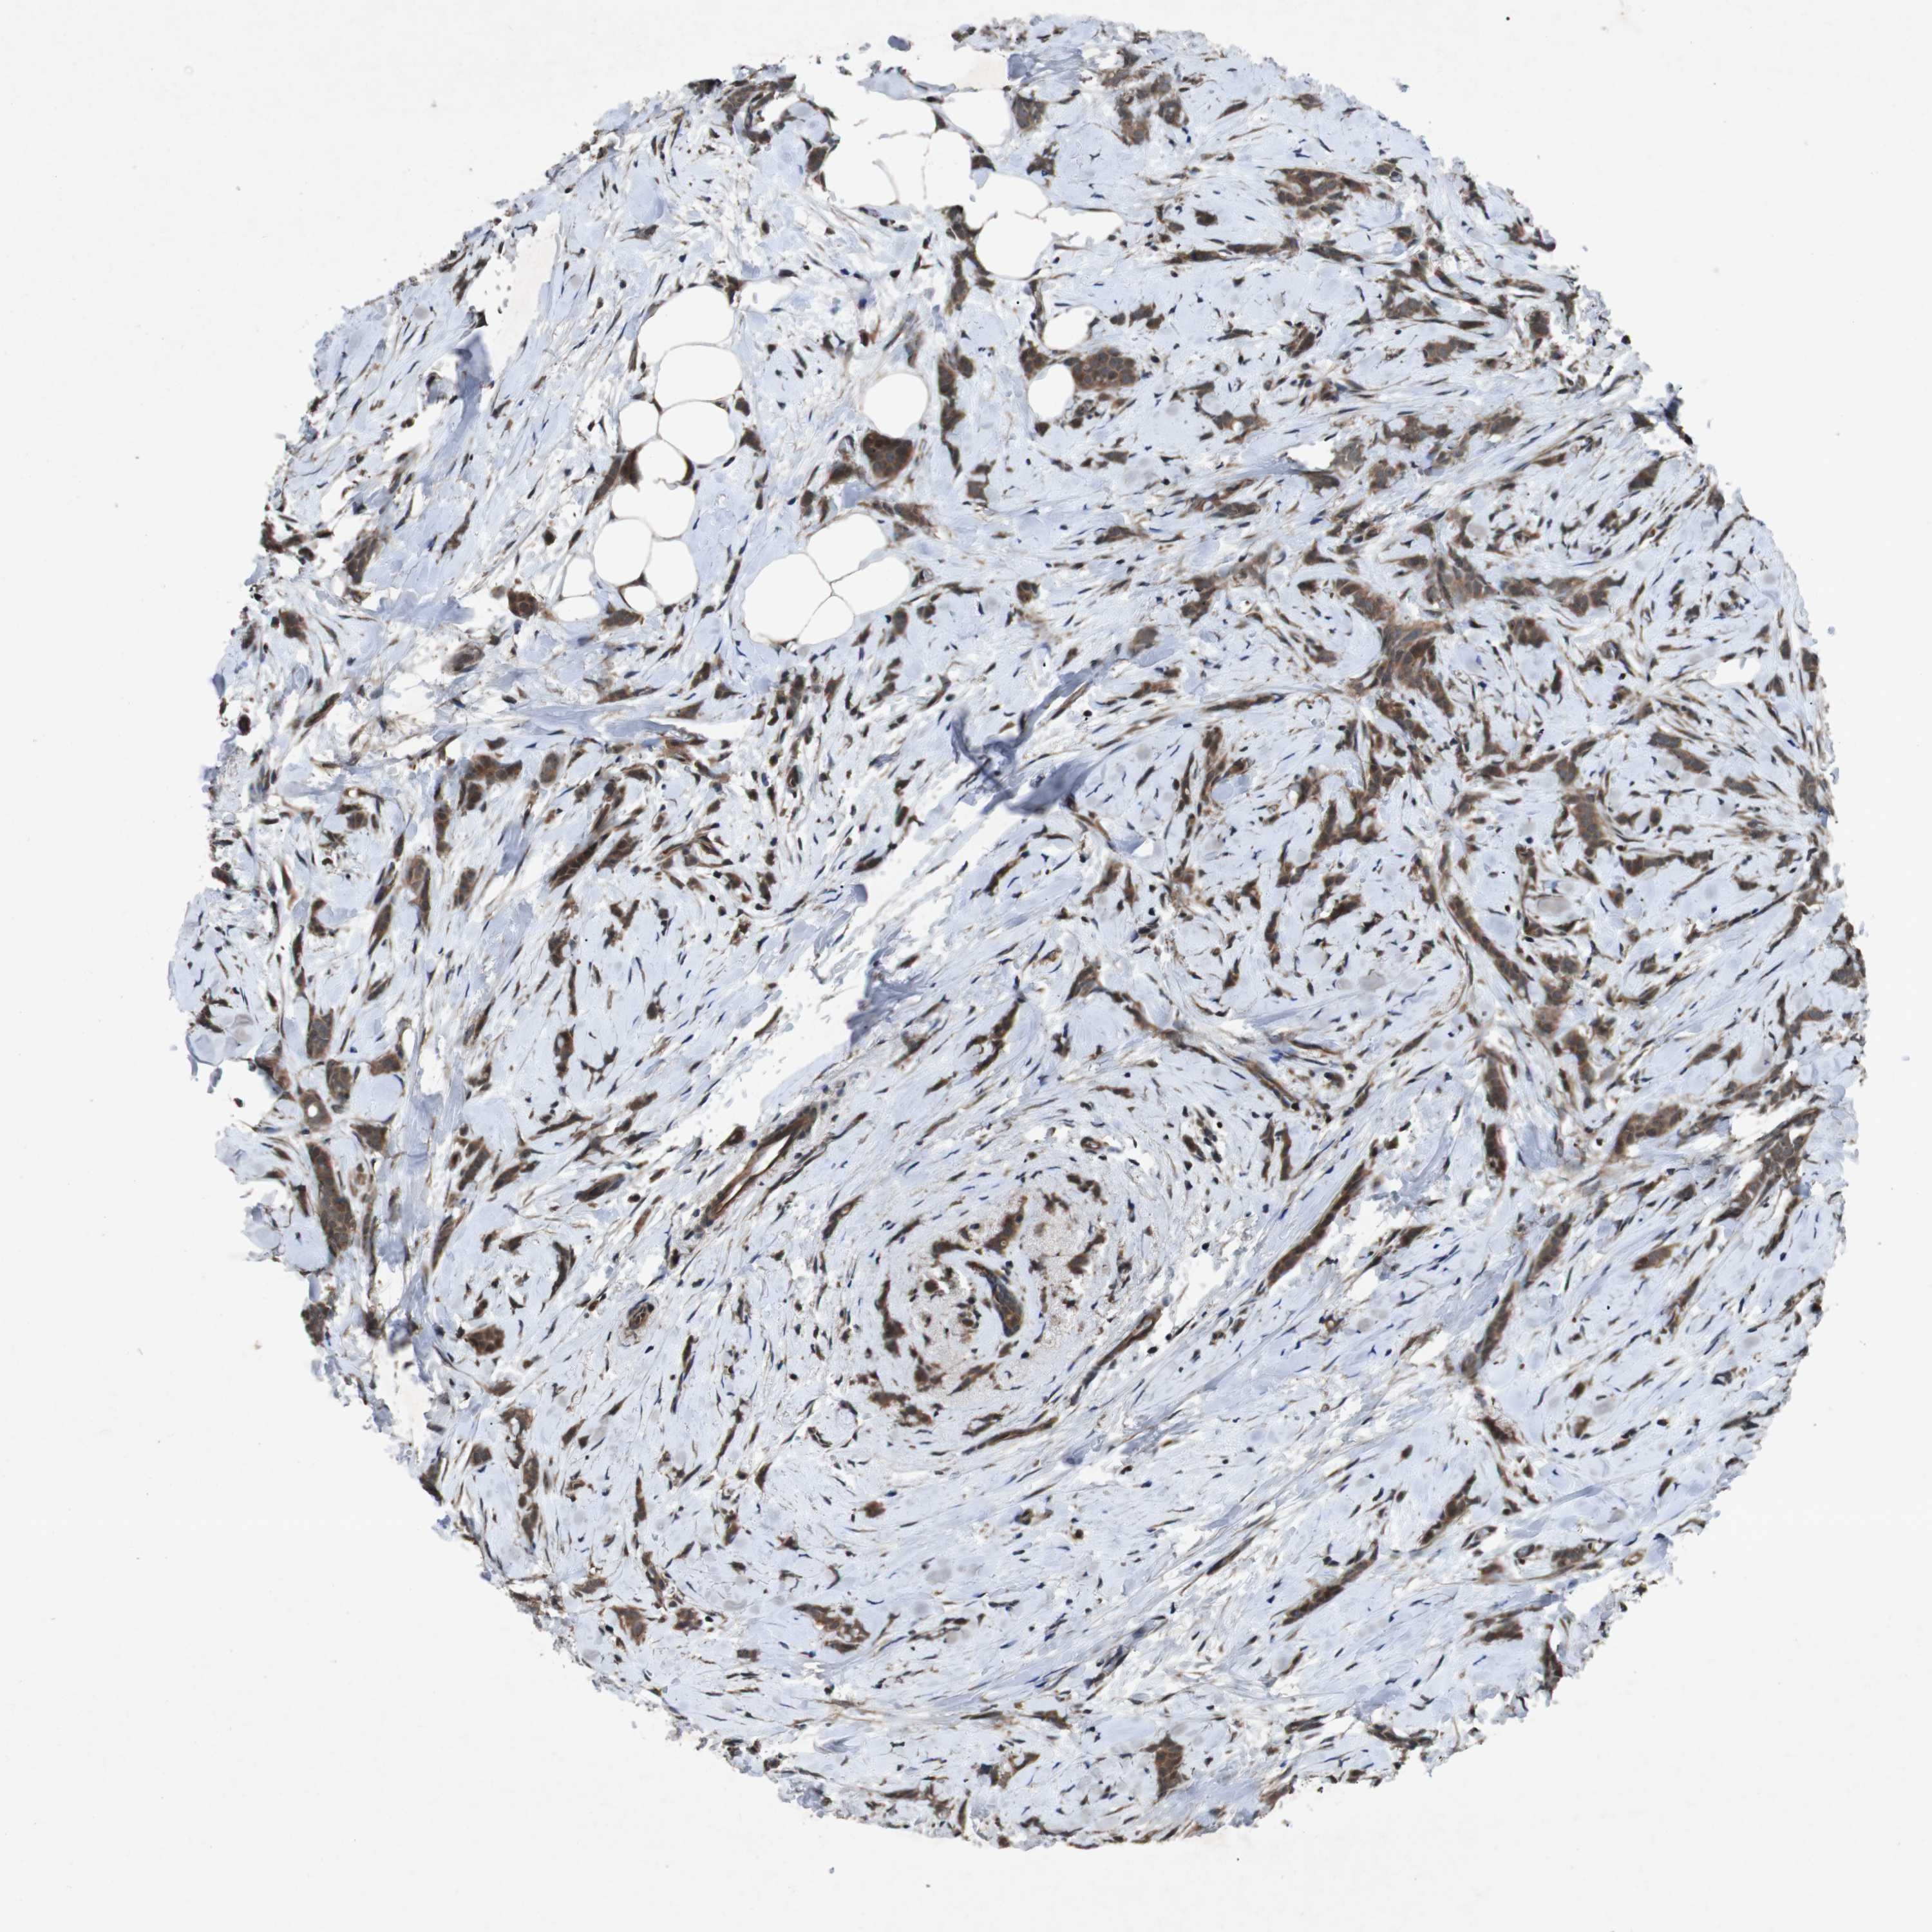

CANCER BREAST CANCER Show tissue menu

BRCA TCGA BRCA VALIDATION PROTEIN EXPRESSION

ANTIBODIES

AND

VALIDATION